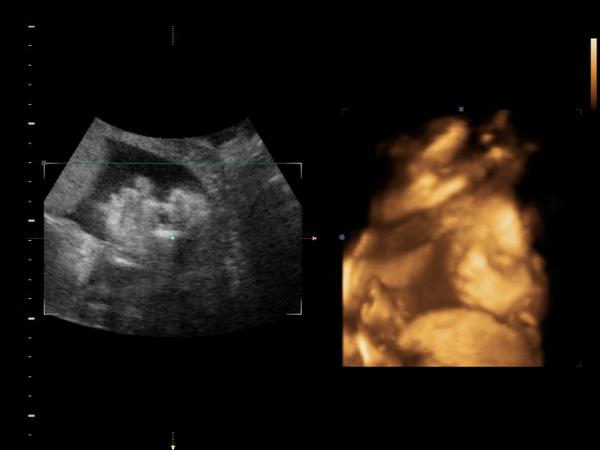

@mishi Ahojky, vše bylo ok 🙂 Malá má už 1100g 🙂 A pořád je v grafu na jedničku 🙂 I když se mi zdá docela velká 😀 Ve čtvrtek jsem byla před Jardou na OGTT a mám to ok 🙂 Jen mě Jarda pokáral za ty moje kilča nahoře ☹ Všichni co mě znají,tak říkají, že těch 10kg nejde vidět, i sama cítím, že kdybych normálně nabrala 10kg, tak budu víc jak bečka 😀 A konečně se povedlo videjko a fotečka malé 🙂 Tak mám radost 🙂 Příští kontrolu, za měsíc jdu k té paní doktorce, tak jsem na ní zvědavá 🙂 Už musím doplatit taky druhou půlku..